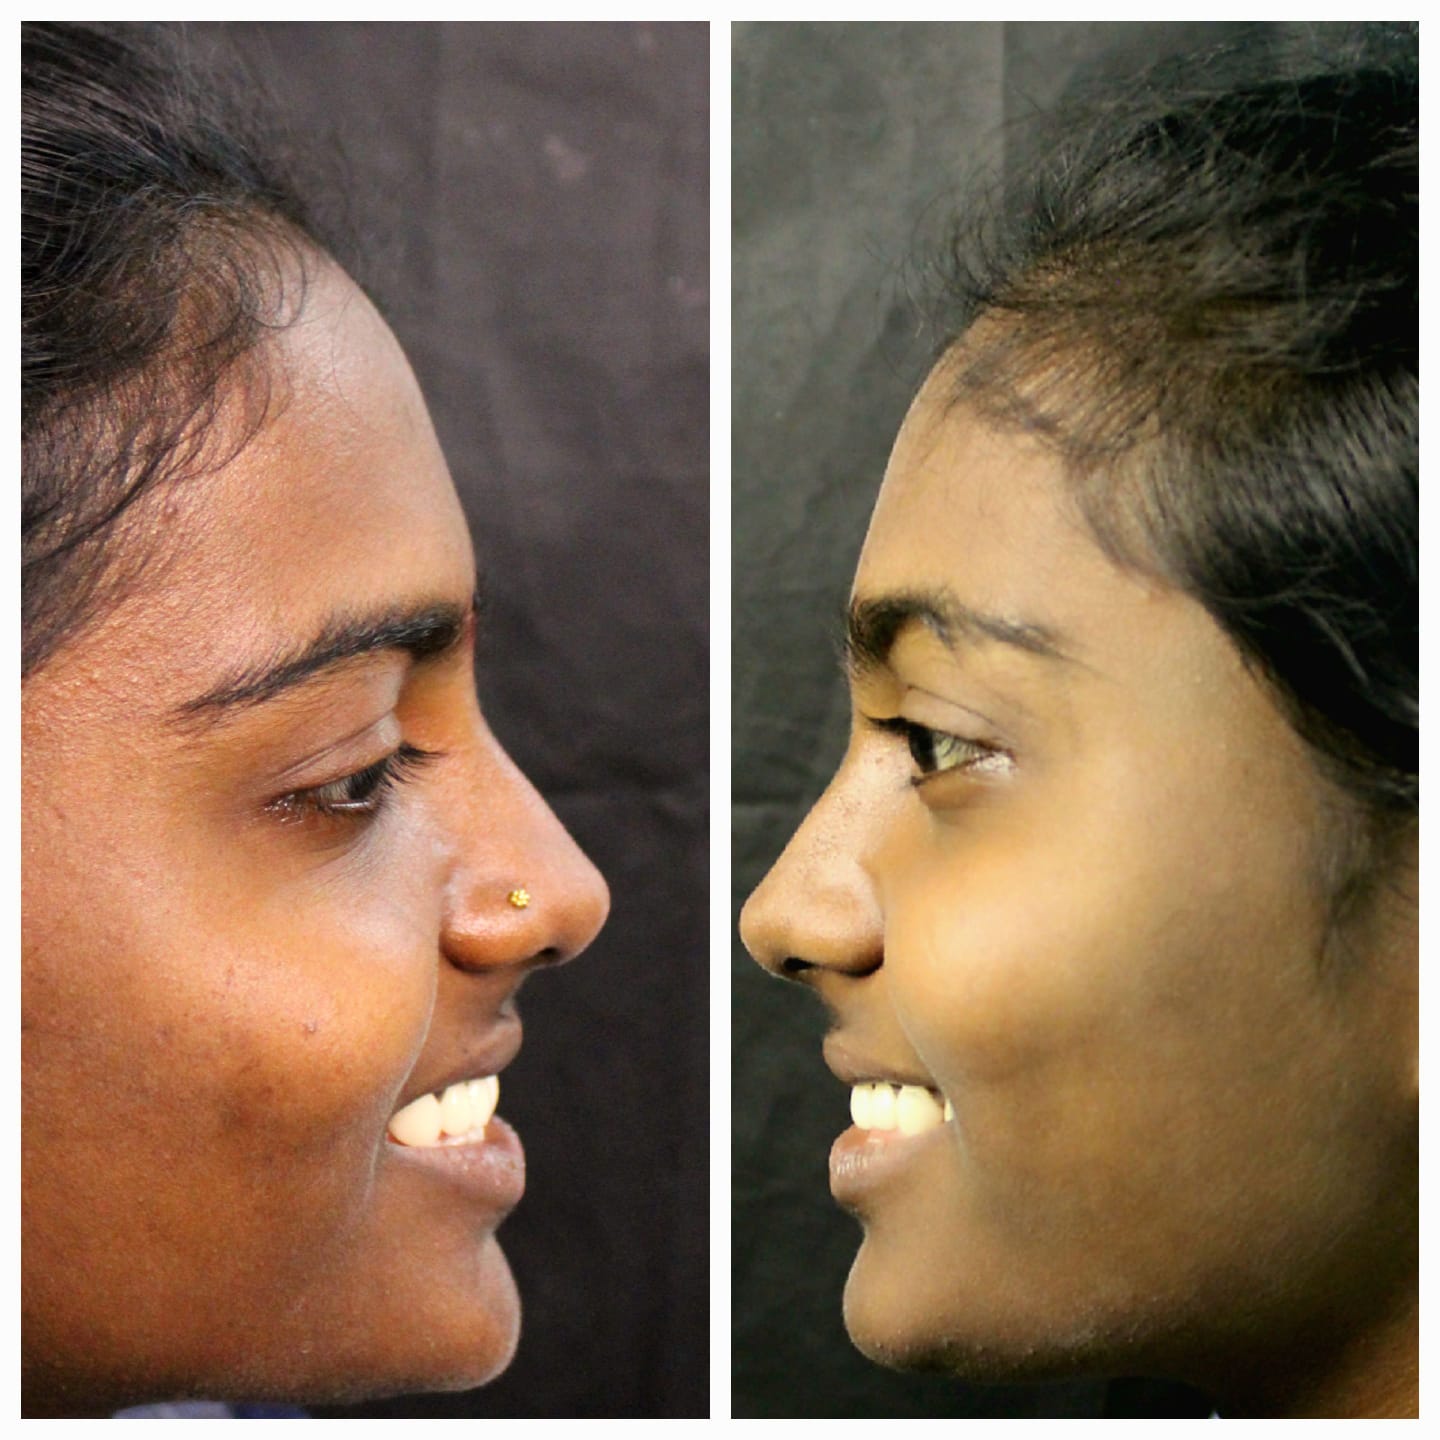

Smile Transformation Results

Real patient results showcasing confident, healthy, natural smiles.

Explore Our Care Moments

Discover insightful visuals highlighting smile transformations, advanced dental procedures, and patient care at our Hyderabad clinic.